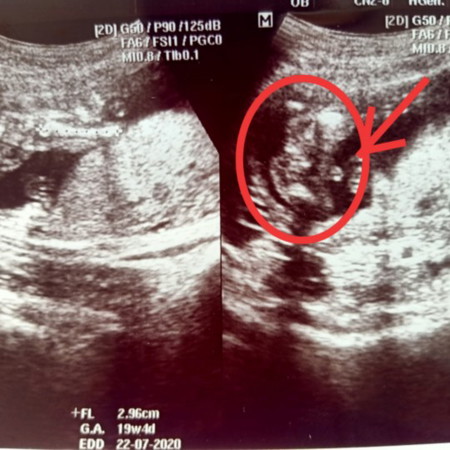

รบกวนแม่ๆ ช่วยดูเพศให้หน่อยค่ะ

แบบนี้ ผช/ผญ ค่ะ

คิดว่าชายค่ะ แต่รอหมอคอนเฟิร์มนะคะ

ถ้าจากภาพคิดว่า ชายค่ะ